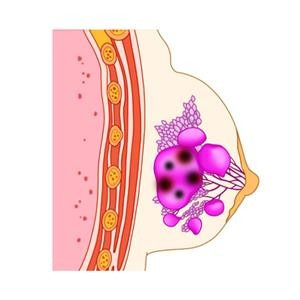

2. 유방암 2기 생존율

유방암 2기는 종양의 크기가 커졌거나 겨드랑이 림프절로 전이가 일어난 단계입니다. 조기 치료를 받으면 높은 생존율을 보입니다.

2기 유방암 생존율

- 5년 생존율: 약 85~92%

림프절 전이 여부, 치료 방식에 따라 차이가 있을 수 있습니다. - 10년 생존율: 약 75~85%

장기적인 관리와 정기 검진이 중요합니다.